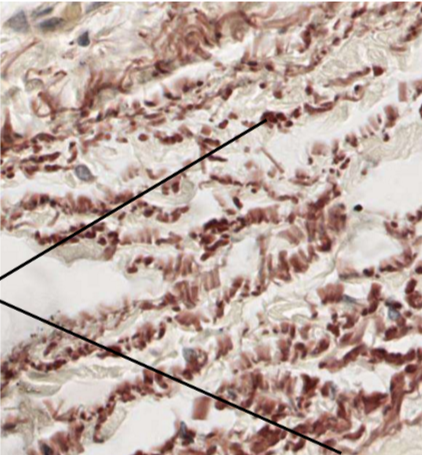

colorant utilisé en immunohistochimie (COLORATION SPÉCIALE) pour mettre en évidence les fibres élastique des tissus conjonctifs

ex:

- derme

- poumon

- pavillon de l’oreille

- artères

- épiglotte

donne un aspect brunatre

provenait initialement du lichen

Dans cette lame, ou sont les fibres d’elastine et quest ce quon peut leur attribuer comme caractéristique

A

elles sont en brun et elles sont isolées (minifil)